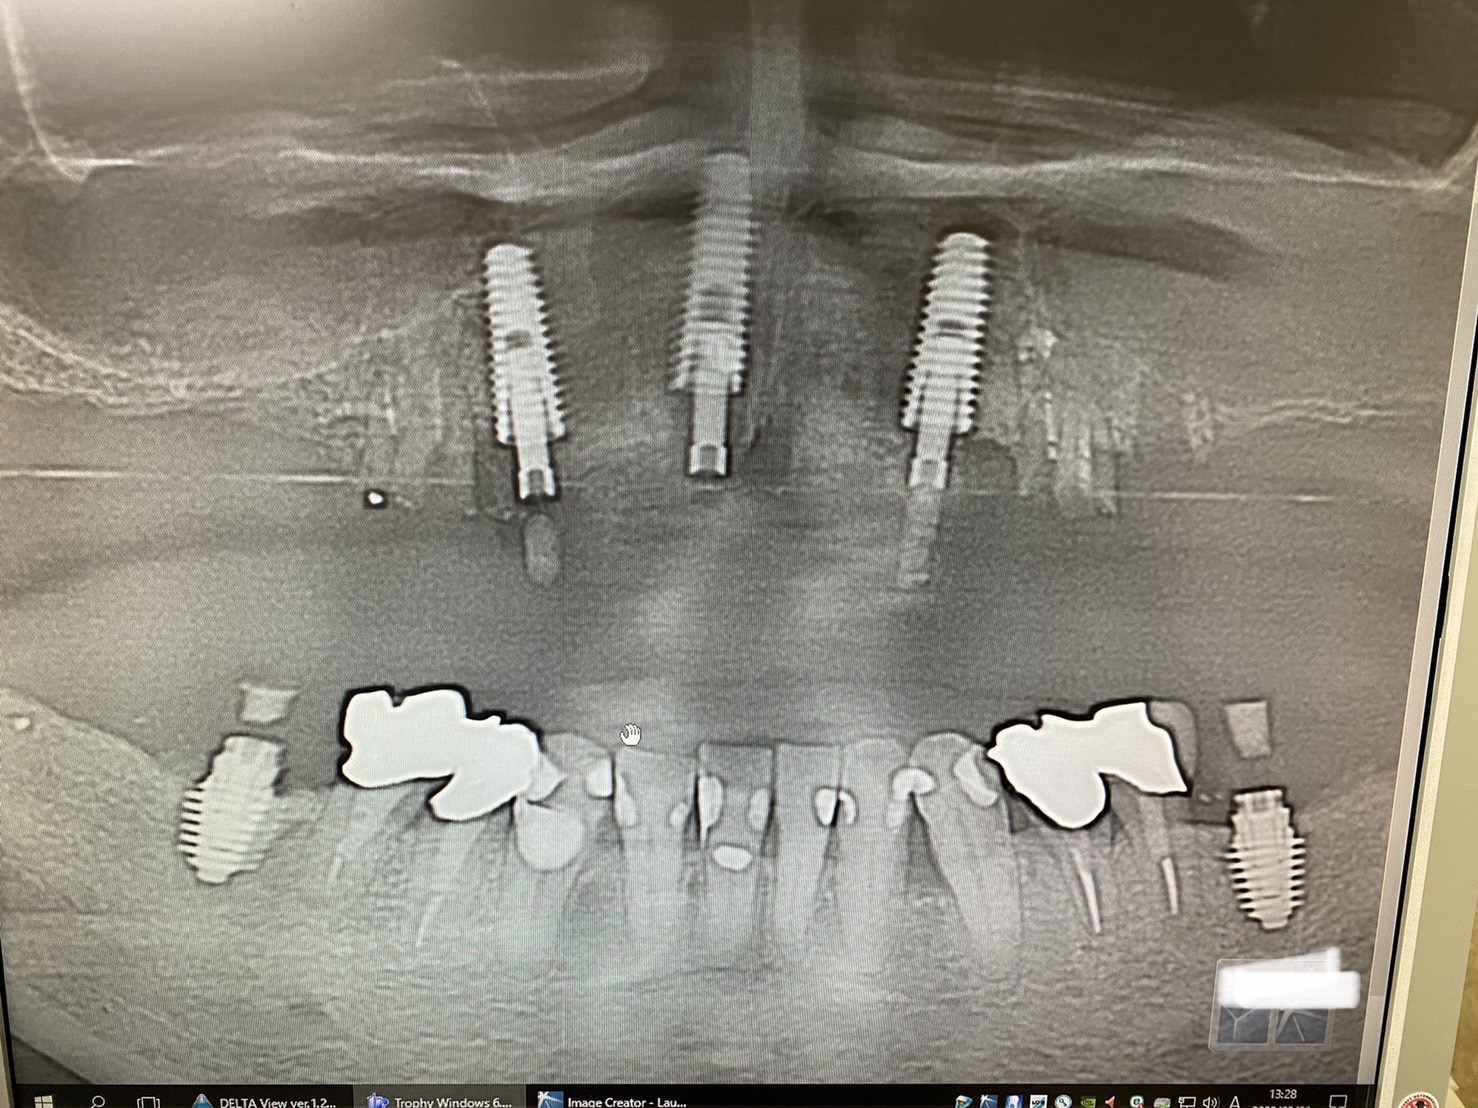

ただいま義歯からの脱却進行中の患者さん、本日は前方エリアのインプラントオペを実地

既存の部分義歯を改造。抜歯。

インプラントオペは3本同時に。

ソケットシールドテクニック(2020年12月4日ブログ参照)、鼻腔底支持、開洞、即時荷重と、、盛りだくさんのテクニックを併用してのオペも60分で全て終了‼︎‼︎‼︎

この方、再来週から奥歯部分のソケットリフトオペも開始(スリーユニットのスクリューリテイン、ブリッジ予定)